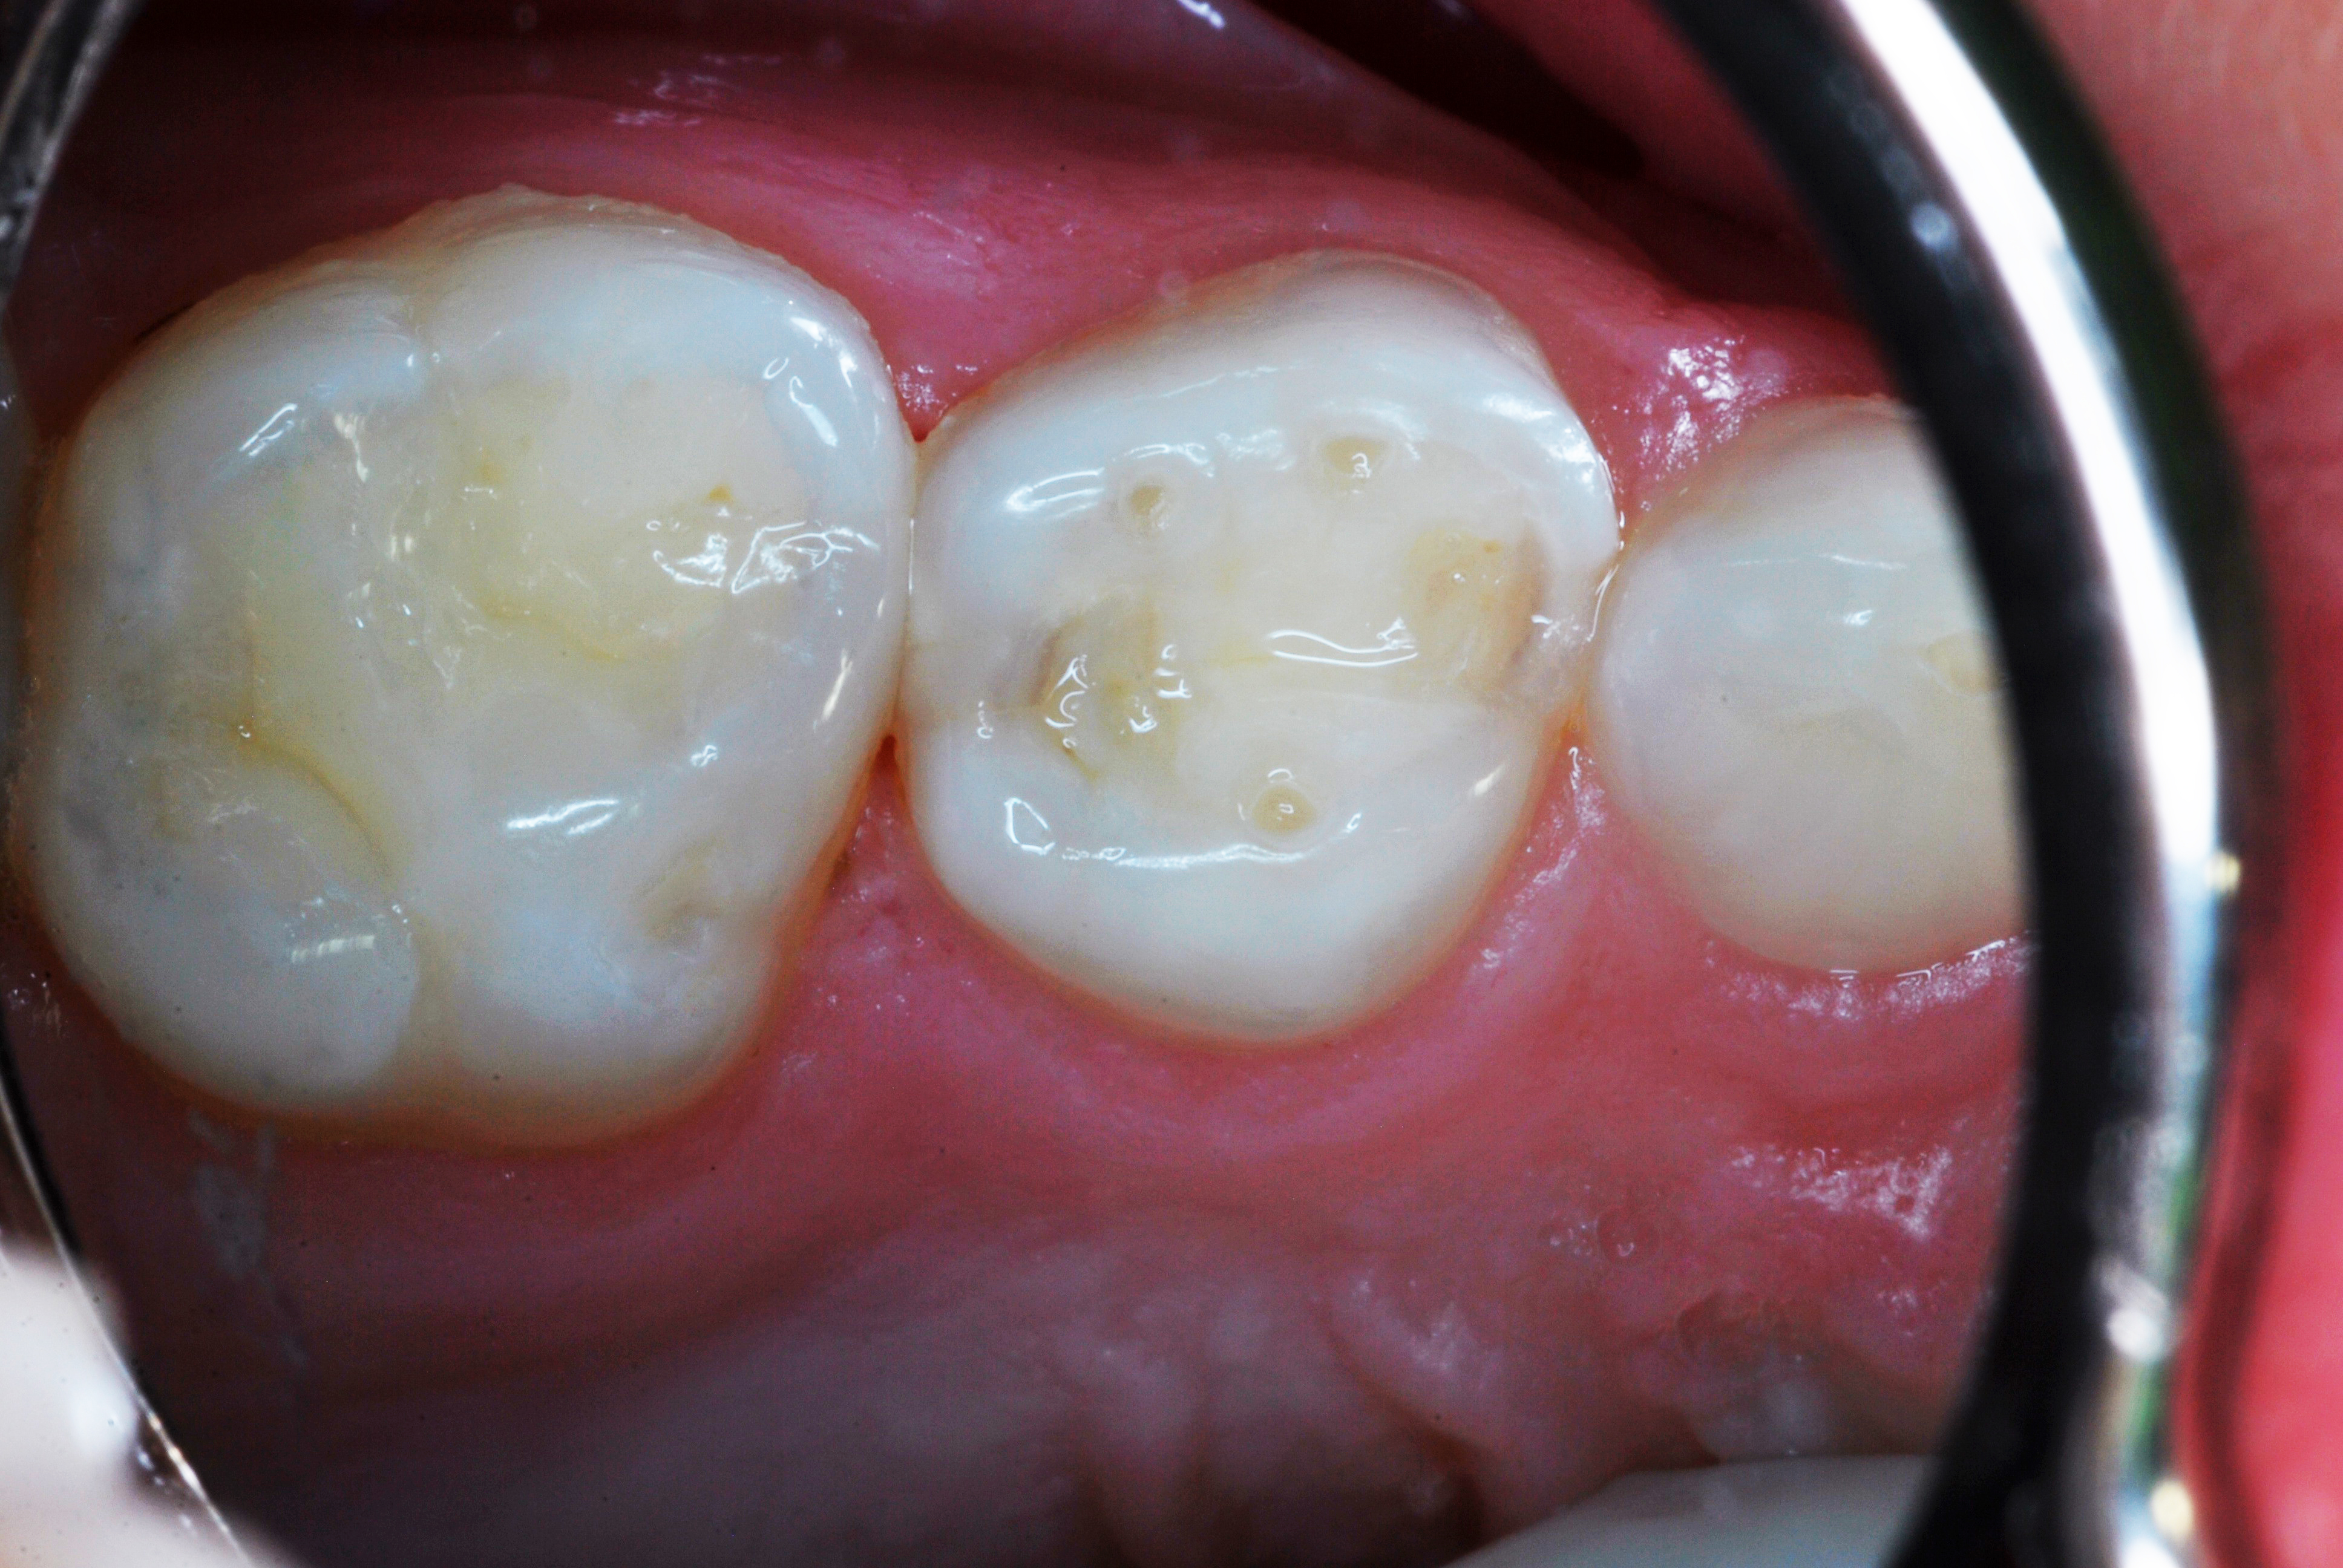

(4.) SDF treated molar in a 3-year-old patient, 4 months after application.

Figure 4